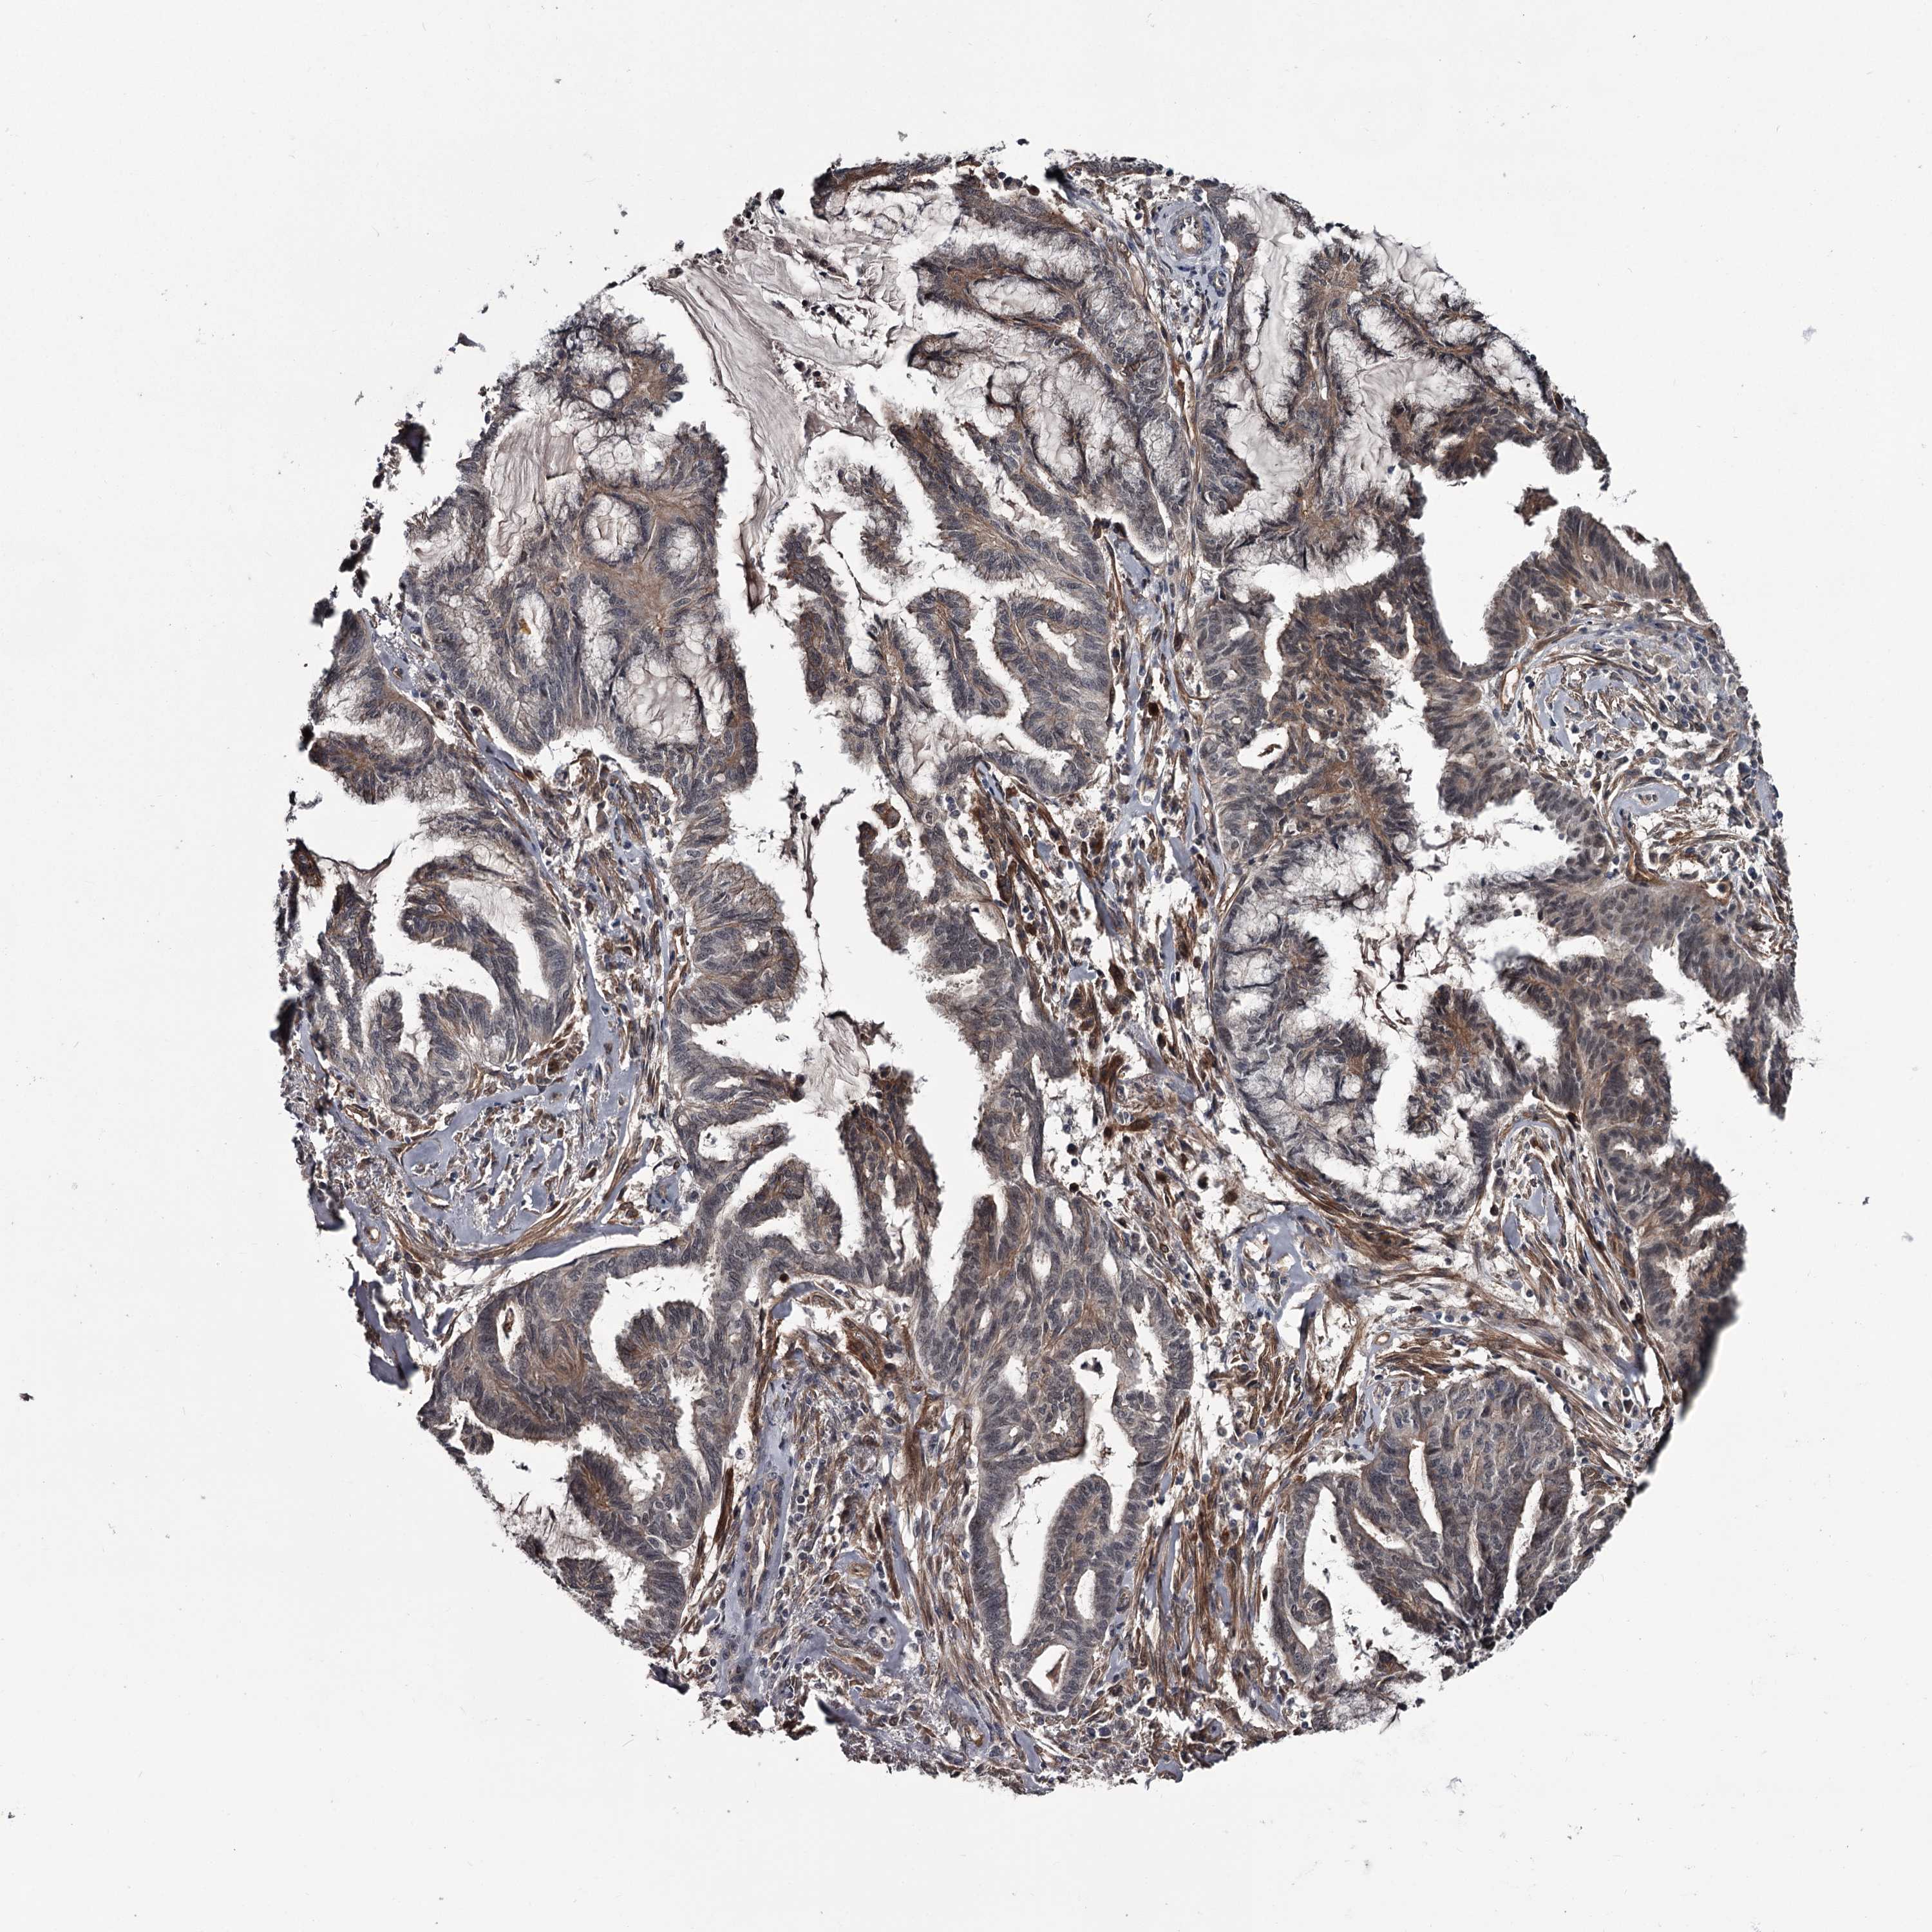

ENDOMETRIAL CANCER - Protein expressioni

A mouse-over function shows sample information and annotation data. Click on an image to view it in a full screen mode. Samples can be filtered based on level of antibody staining by selecting one or several of the following categories: high, medium, low and not detected. The assay and annotation is described here.

Note that samples used for immunohistochemistry by the Human Protein Atlas do not correspond to samples in the TCGA dataset.

Antibody stainingi

Antibody staining in the annotated cell types in the current human tissue is reported as not detected, low, medium, or high, based on conventional immunohistochemistry profiling in selected tissues. This score is based on the combination of the staining intensity and fraction of stained cells.

Each image is clickable and will lead to virtual microscopy that enables deeper exploration of all samples and also displays staining intensity scores, fraction scores and subcellular localization as well as patient and tissue information for each sample.

Antibody HPA038562

Staining

High

Medium

Low

Not detected

Intensity

Strong

Moderate

Weak

Negative

Quantity

>75%

75%-25%

<25%

None

Location

Nuclear

Cytoplasmic/membranous

Cytoplasmic/membranous,nuclear

Adenocarcinoma, NOS

Adenocarcinoma, metastatic, NOS